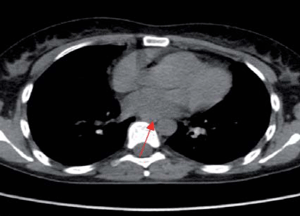

Mujer de 35 años, consulta hace seis años por cuadro de tres meses de evolución dado por adenopatías cervicales, astenia y adelgazamiento. TC: nódulos pulmonares, engrosamiento intersticial bilateral y adenopatías cervicales, mediastinales, hiliares, abdominales, retroperitoneales e inguinales (figura 3) y (figura 4). Biopsia ganglionar cervical: proceso granulomatoso crónico no necrotizante compatible con sarcoidosis. Electrocardiograma (ECG) y ecocardiograma normales. Recibe prednisona durante 18 meses manteniendo estabilidad clínica, imagenológica y funcional respiratoria.

Figura 3: TC: micronódulos pulmonares bilaterales cisurales y subpleurales, engrosamiento intersticial.